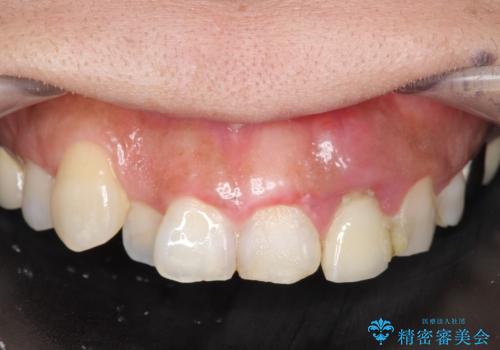

- 左上2番目の歯がグラグラするので診て欲しいといらっしゃった方の症例です。

左上2番目の歯は歯根が破折してため抜歯し、左上123のブリッジによる欠損補綴を行いました。

左上4、5番目の歯は根尖病変を認めたため再根管治療を行い、オールセラミッククラウンによる補綴を行いました。

なお左上4に関しては縁下歯質を改善するため、歯冠挺出を行っております。